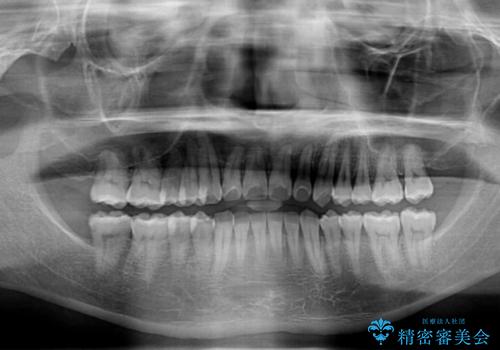

- 前歯のデコボコとクロスバイトを気にして来院された患者様です。

インビザラインでもワイヤー装置でも矯正治療は可能でしたが、煩わしい自己管理なしに短期間で治療を行いたいとのことで、目立たないワイヤー装置にて治療を行うこととしました。

- 1年1ヶ月